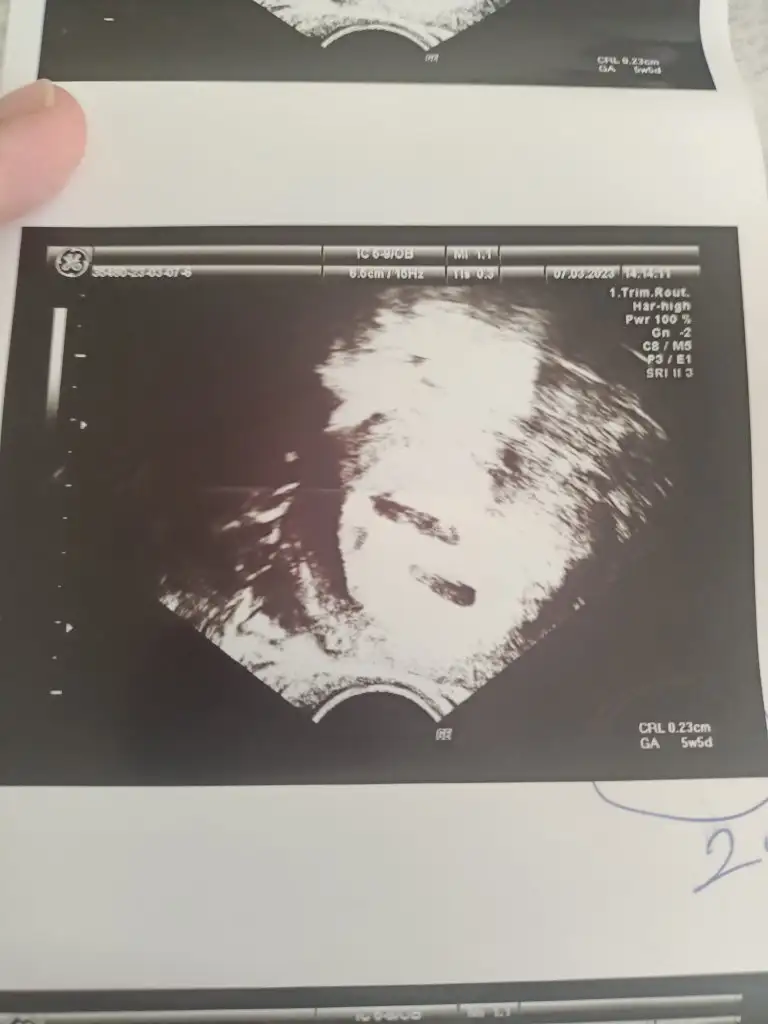

Canım 5+6 dayız dayanamadik eşimle özele gittik. Açıkçası birşey beklemeyi ummuyorduk daha küçük olduğu için gene sadece kese görünür diye düşünüyorduk. İlk önce karından ultrasonla baktı miniğim yeni oluşmuş kalp atışını duyduk pıt pıt🥰 sonra doktor kesenin hemen yakininda bir oluşum olduğunu düzgün goruntude olduğunu keseye benzettigini ama diğerinden kese boyutunun daha küçük ve icininde boş olduğunu söyledi. Sonrasında dediki bence ikiz gebelik olarak başlamış olabilir ama kesenin biri küçük içi boş ve kaybolacak muhtemelen bu tek gebelik dedi. Sonra çıkmadan önce vajinal ultrasonla da bakalım mi bebeğe zararı varmı kanama alanı da olabilir dedi bende tabiki bakalım dedim. Vajinal ultrasonda bir baktık ki digeride keseymis ve içi dolu orda da bebiş var ve çok şükür az da olsa ondan da kalp atışı duyduk😍 galiba bu ikiz meselesi biraz da his meselesi çünkü doktor böyle bişey görmemesine denemesine rağmen ben surekli böyle hissetmistim. Allah'ıma binlerce kez şükürler olsun inşallah sağ salim ikisinide kucağımıza almak nasip olur inşallah 🥰🤲🧿🧿🧿🧿🧿

Evet ikinci vajinal ultrasonda bile gene çok zorladı doktor bir türlü sabitleyemedi kalp atışını çok minik digerinden bir hafta kadar küçük ama uzun uğraş sonucu gördük çok şükür doktorda çok nazlı dedi😊Amin canım sağolasın inşallah ikisini de sağ salim kucağımıza alırız 🤲🙏🧿🧿🧿